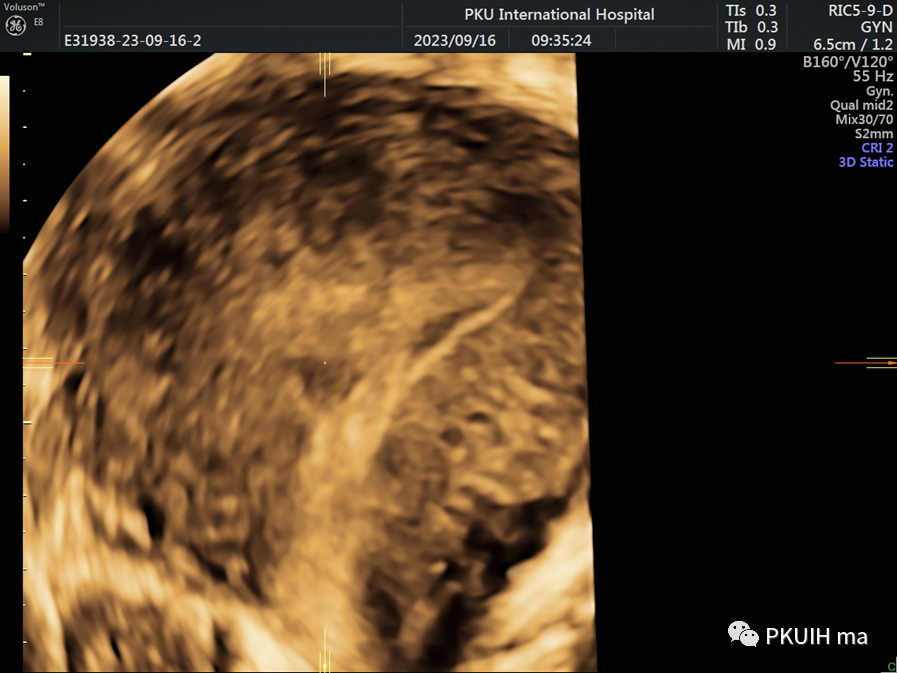

三维超声显示宫内环在子宫内发生扭转